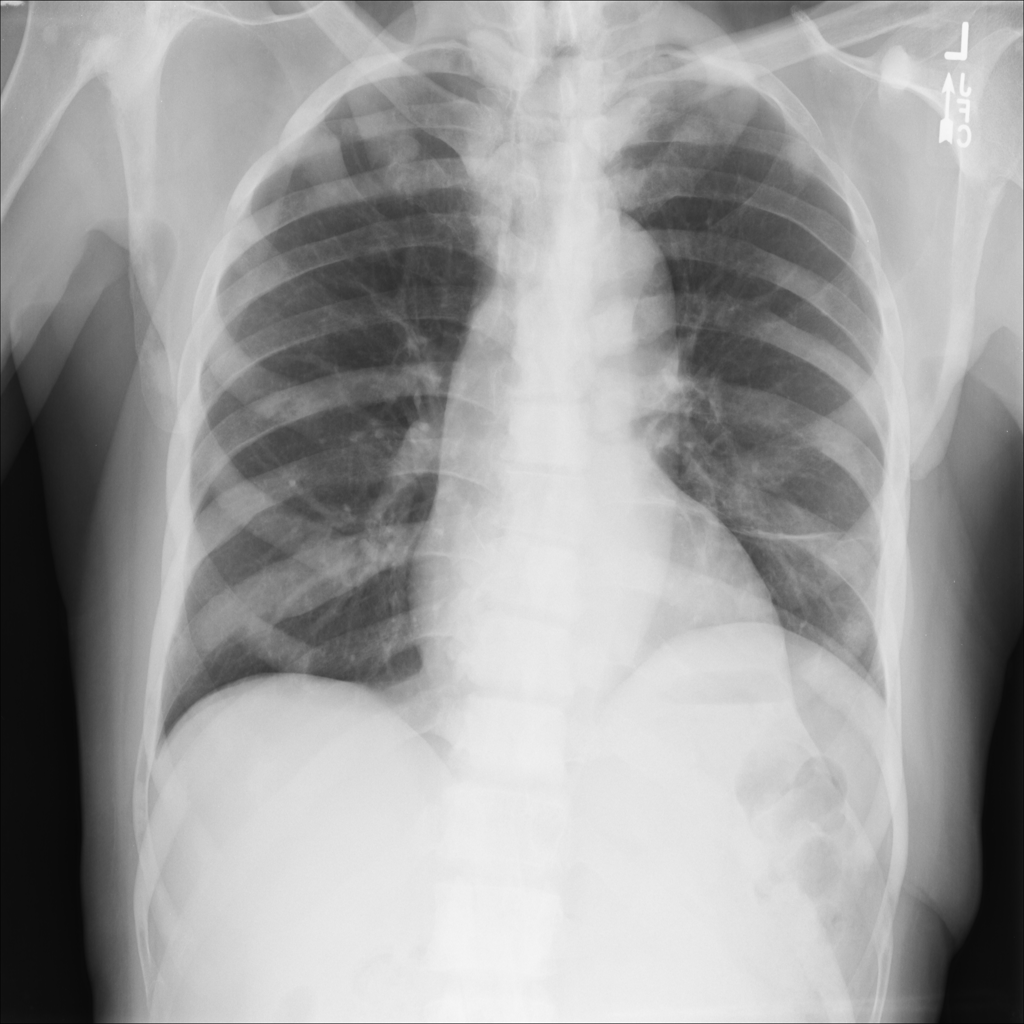

Figure 2: PCA component visualization. Following [8], the PCA is computed between patches of images that are in the same column, and the first 3 components are shown. This is done for X-ray, CT, and MRI scans. Thresholding is used on the first component to remove the background.

In this section we will show qualitative results of DINOv2 features using principal component analysis (PCA) performed on DINOv2 patch features on X-ray, CT, and MRI scans, following the method delineated in [8]. We will also provide organ segmentation results of linear compared U-Net decoders.

PCA visualization. Figure 2 shows the first three PCA components. The PCA is computed between patches of images that are in the same column, and the first 3 components are shown for X-ray, CT, and MRI scans. Thresholding is used on the first PCA component to remove the background. Just like in natural images [8], the colors of the three PCA components correspond well with the same parts of images in the same category. This is an easier task however, compared to natural images, because there is less variability between examinations on medical images compared to natural images.